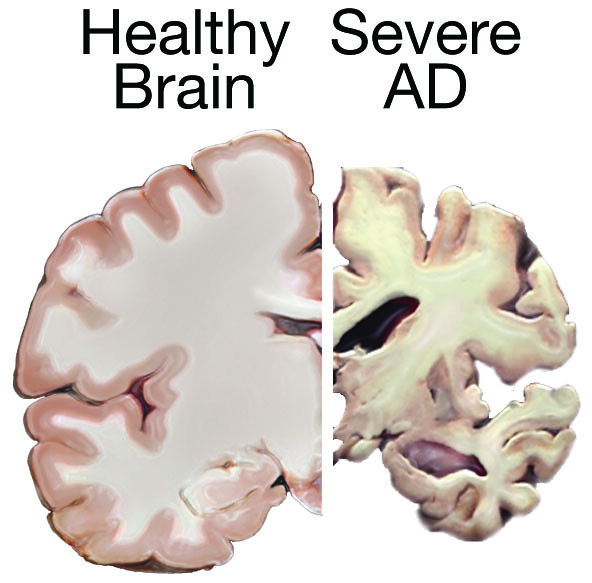

The Healthy Brain (left) and the Alzheimer’s Brain (right) | Download …

Macroscopic appearance of the brain of a subject (Case 2) with dementia …

Why Do Ventricles Enlarged In Alzheimer’s – DementiaTalkClub.com

Cross-section of the Human Brain with Alzheimer`s Disease Stock Vector …